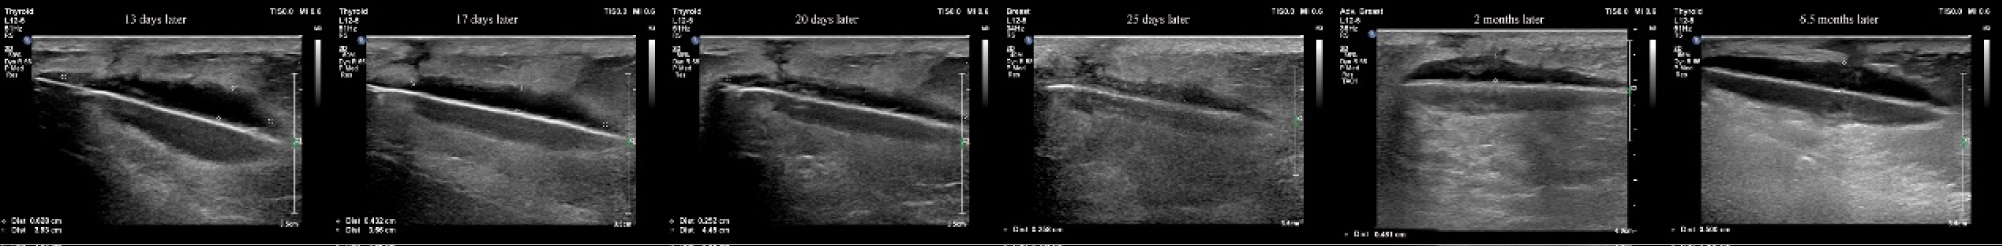

On the seventh postoperative day (after the stage II surgery), the wound tissue was liquefied and broken (Figure 2). We used a Chinese traditional cupping technique to aspirate about 6 ml of liquid two days later. A day later, the skin appeared intact, and then we began to monitor ultrasound changes without any more aspiration. Superficial ultrasound showed no obvious liquefaction at the surgical field on the second day. A small amount of liquefaction was found at the stimulator position under superficial ultrasound six days later. The liquefaction area further enlarged ten days later. Similar images appeared on an ultrasound thirteen days later. Seventeen days later, the superficial ultrasound showed reduced liquefaction at the stimulator position, while the liquefaction tracked to the S3 foramen along the wire. Above the S3 foramen, the lead placement site had some swelling. Ultrasound showed progressively reduced liquefaction at stimulator position but increased liquefaction around the puncture area with swelling. The patient was started on oral antibiotics. Three days later, the fat liquefaction finally resolved and ultrasound showed progressively reduced liquefaction both at the stimulator position and around the lead entry site. She was regularly followed up by ultrasound and we measured the depth of liquefaction area around both the stimulator position and puncture area to note the trend of the change of fat liquefaction (Figure 3).

Figure 3: We used ultrasound to monitor the liquid at the stimulator position and measure the distance of the liquid area. The depth of the liquid dark area was reduced from 0.628 cm to 0.258 cm within 2 weeks. View Figure 3